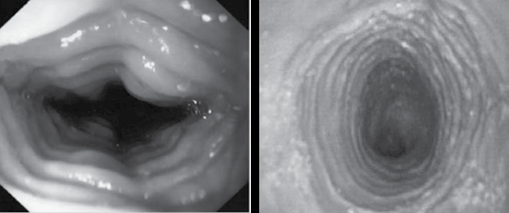

Observe as imagens a seguir.

É correto afirmar que as imagens são sugestivas de